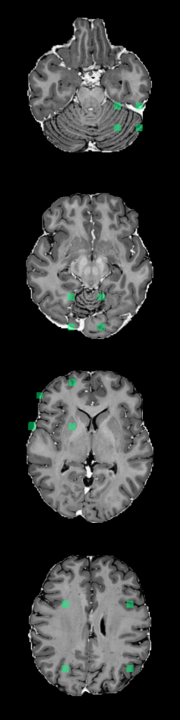

Using the synthetic test data described in Section 3.1, we evaluate the method’s ability to detect different types of outliers. Figure 3 displays the model’s response to a sink/source deformation outlier and a normal sample. The plot includes abnormality scores for individual slices across the entire volume. Slices that include the artificially deformed sphere produce a strong and consistent activation (Figure 3, red). Meanwhile, normal slices elicit only weak activations (Figure 3, blue).

Since FPI is trained on synthetic examples, i.e., interpolated patches, it is able to detect other similar classes of synthetic anomalies relatively easily. In comparison, reconstruction-based methods have difficulty identifying these synthetic anomalies because they have minimal intensity differences and occupy less than 1% of the total imaging volume of a subject. Although the reconstruction-based methods have high scores for pixel-level AUROC, the DICE scores are quite low (Table 1). This is because the DICE score focuses more on anomalous pixels, while AUROC can be partly inflated by a large number of normal background pixels. These blank pixels are easy to reconstruct without error. This increases the number of true negatives, which in turn decreases the false positive rate (x-axis of the ROC curve) and increases the area under the curve. In contrast, pixels in tissue regions often have some level of reconstruction error because there is a limit to the amount of detail that the models can recreate. Since the synthetic anomalies have similar intensity values, they also produce similar reconstruction error. When the reconstruction error is averaged across the entire volume, the contribution from the synthetic anomaly is hidden by the contributions from other healthy regions, which leads to a poor subject-level AUROC. Meanwhile, FPI produces very low anomaly scores for normal tissue and activates specifically for certain types of features, as seen in Figure 3.